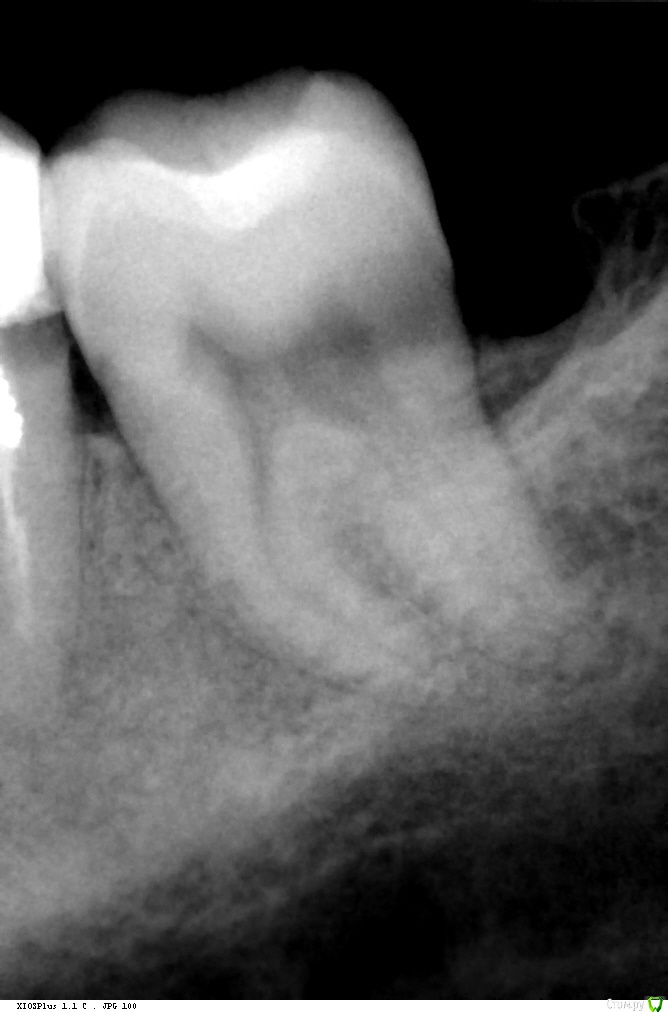

super Опубликовано 11 января, 2016 Поделиться Опубликовано 11 января, 2016 Доброго времени суток! Удаляю два зуба (снимки прилагаются). Будет ли возможность поставить импланты через несколько лет, если я откажусь от костного материала?В стоматологии расписали план, костный материал идёт опционально. Дескать, можно и без него, но лучше с ним, если планируете импланты (а я планирую через 2-3 года). Дополнительная информация:* Костный материал «БИ-ОСС» 0,5 гр.* 6-ка: пломба вылетела вместе со штифтом (снимок старый). Стоматолог сказал, что без шансов, надо удалять.* 7-ка: в 2-х стоматологиях сказали, что кариес корня и рекомендовали удалить. Спасибо :-) Ссылка на комментарий